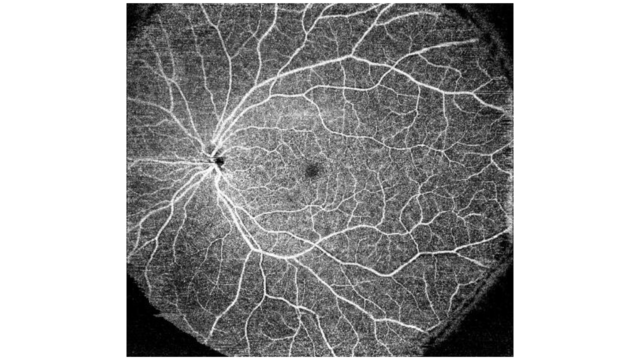

Topcon’un SS-OCT Angio™ ürünü, OCT anjiyografiyi Swept-Source teknolojisiyle birleştirir.

Tescilli bir görüntü işleme algoritması olan OCTARA™, yüksek hassasiyetli anjiyografik algılama4 sağlayarak, koroid ve daha derin retina katmanlarında bile vasküler yapıların görselleştirilmesine olanak tanır.

OCTARATM, aynı konumda elde edilen çoklu OCT B-Tarama görüntülerini kullanarak vasküler akıştan kaynaklanan sinyal değişikliklerini çıkaran görüntü işleme teknolojisidir. Mikro damarlardaki düşük kan akışını tespit etmede yüksek hassasiyet gösterir

Swept Source teknolojisi ve OCTARA™, daha derin yapıların daha az derinlik bağımlı sinyal düşüşüyle görselleştirilmesini sağlar3. Ayrıca, 1μm dalga boyu, medya opasiteleri olan hastalar için OCT Anjiyografi görüntülemesini mümkün kılar.

Saniyede 100.000 A-Tarama, görünmez tarama çizgileri ve SMARTTrack™ göz takip sistemi ile Triton, yoğun bir veri setini hızla yakalar ve retina mikrovasküler akış ağının En Face OCT Anjiyografi görüntüsünü sunar.